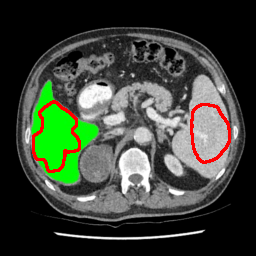

Our primary findings comparing the proposed model to baseline fully-supervised models when segmenting the liver from the LiTS dataset are reported in Table 1. The reported results demonstrate that our SAM-Mix model consistently achieves higher Dice scores compared to the fully supervised baselines as well as the two-stage SAM-PP method. Against U-Net, the best-performing fully supervised method, the SAM-Mix variant trained on 50 segmentation labeled slices (SAM-Mix-50), achieves a Dice score improvement of 5.9%. In terms of Hausdorff distance, while the fully-supervised baselines do slightly outperform SAM-Mix-5 and SAM-Mix-100, SAM-Mix-50 does achieve a lower Hausdorff distance by 22.38%. Qualitative evaluation as shown in Figs. 3 further affirms the superiority of SAM-Mix over baseline and existing fully-supervised methods as well as the two-stage SAM-PP variants. Furthermore, the boxplot visualization in Fig. 2 showcases consistently improved performance by SAM-Mix outperforming all the fully supervised and semi-supervised methods.

To test the generalizability of SAM-Mix, we validate it on a cross-domain dataset (TotalSegmentator). As reported in Table 2, the segmentation performance of SAM-Mix on the cross-domain task is as promising as the in-domain results. Despite the data shifts, from LiTS to TotalSegmentator, SAM-Mix outperforms all of the baseline models in terms of generalizability, by significant margins. SAM-Mix-50 achieves a Dice score improvement of 25.4%, and a lower Hausdorff distance by 62.26% compared to the best-performing full-supervised U-Net model. These results further validate the few-shot capabilities and establish our SAM-Mix as a well-generalized tool for medical image segmentation.